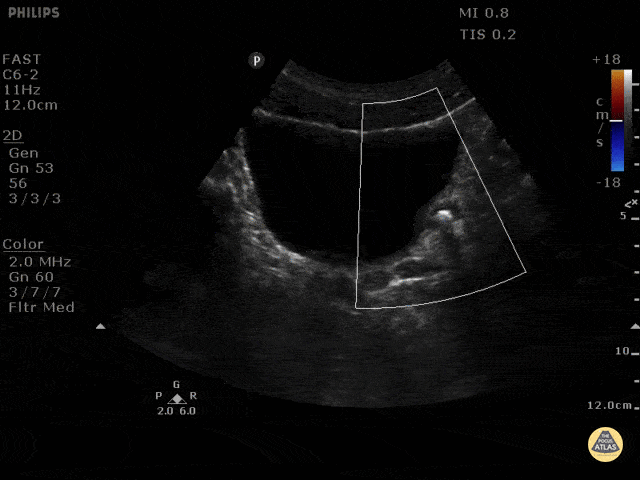

Ultrasonographic color doppler twinkling artifact is a phenomenon that may aid in the detection of nephrolithiasis. Twinkling artifacts can be seen on color doppler ultrasounds when applied to stationary, highly echogenic objects, generating a false sense of movement on color doppler. The reason this occurs is unclear. Seen here is a left ureterovesicular junction stone with a positive twinkle artifact. Maria Perez; Emergency Registrar; St Vincent’s Hospital; Melbourne - Australia